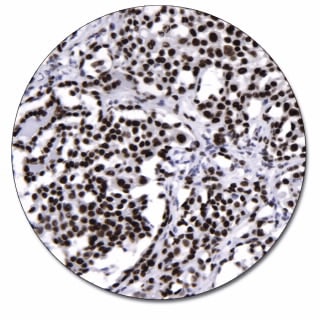

WT1 is a gene involved in the induction of Wilms' tumor, a pediatric renal malignancy. Wilms' tumor 1 protein regulates transcription of other genes and can function both as a transcriptional activator and repressor. The antibody reacts with all isoforms of the full-length WT1 and also identifies WT1 lacking exon 2-encoded amino acids. Results aid in the classification of Wilms' tumors, malignant mesotheliomas and acute leukemias.

Alternate splicing of the WT1 transcript gene results in four distinct mRNA species which are present in different amounts. The predicted molecular weight of the WT1 protein ranges from 46 to 49 kDa depending on the mRNA species however, the WT1 proteins derived from cells migrate at 50 to 55 kDa in SDS-PAGE (4). This antibody recognizes an epitope found in the amino terminal 84 encoded amino acids of WT1. It reacts with all isoforms of the full-length WT1 and also identifies WT1 lacking exon 2, frequently found in subsets of sporadic Wilms' tumors. In immunoprecipitation assays, the antibody has been shown to recognize full-length and in vitro translated WT1. It also detects full-length denatured WT1 (55 kDa) in Western blots of WT1 baculovirus-infected cell lysates (1). See package insert for reference(s).